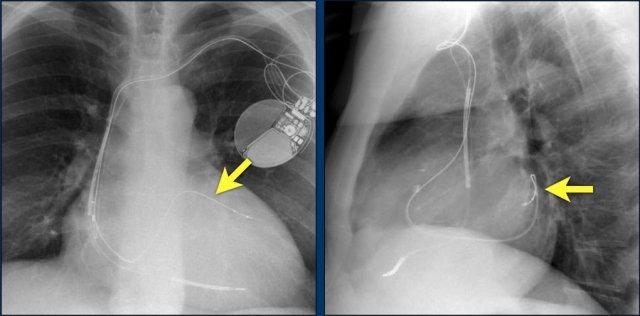

Bệnh nhân này đã được sửa chữa ba van:

- Van hai lá

- Van ba lá

- Van động mạch chủ

Có máy tạo nhịp tim với điện cực thượng tâm mạc.

Phương án này được lựa chọn vì người ta cho rằng điện cực đặt theo đường thông thường vào thất phải sẽ ảnh hưởng quá nhiều đến chức năng của van ba lá nhân tạo.

Mũi tên trắng chỉ vào van động mạch chủ.

Mũi tên vàng chỉ vào van hai lá.